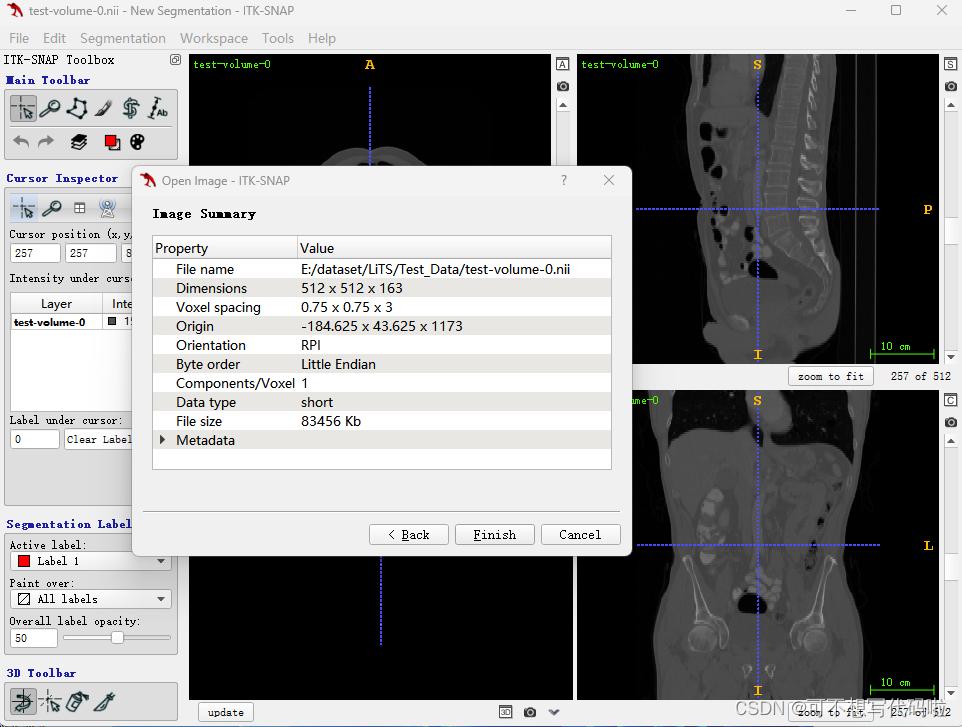

以打开测试集样本为例。

选择文件后,点击Next,就会显示图像的属性和x、y、z轴视图。鼠标点击任一视图的位置并拖动,可以显示相应位置的平面视图。每个视图的右下角都会显示切片位置。